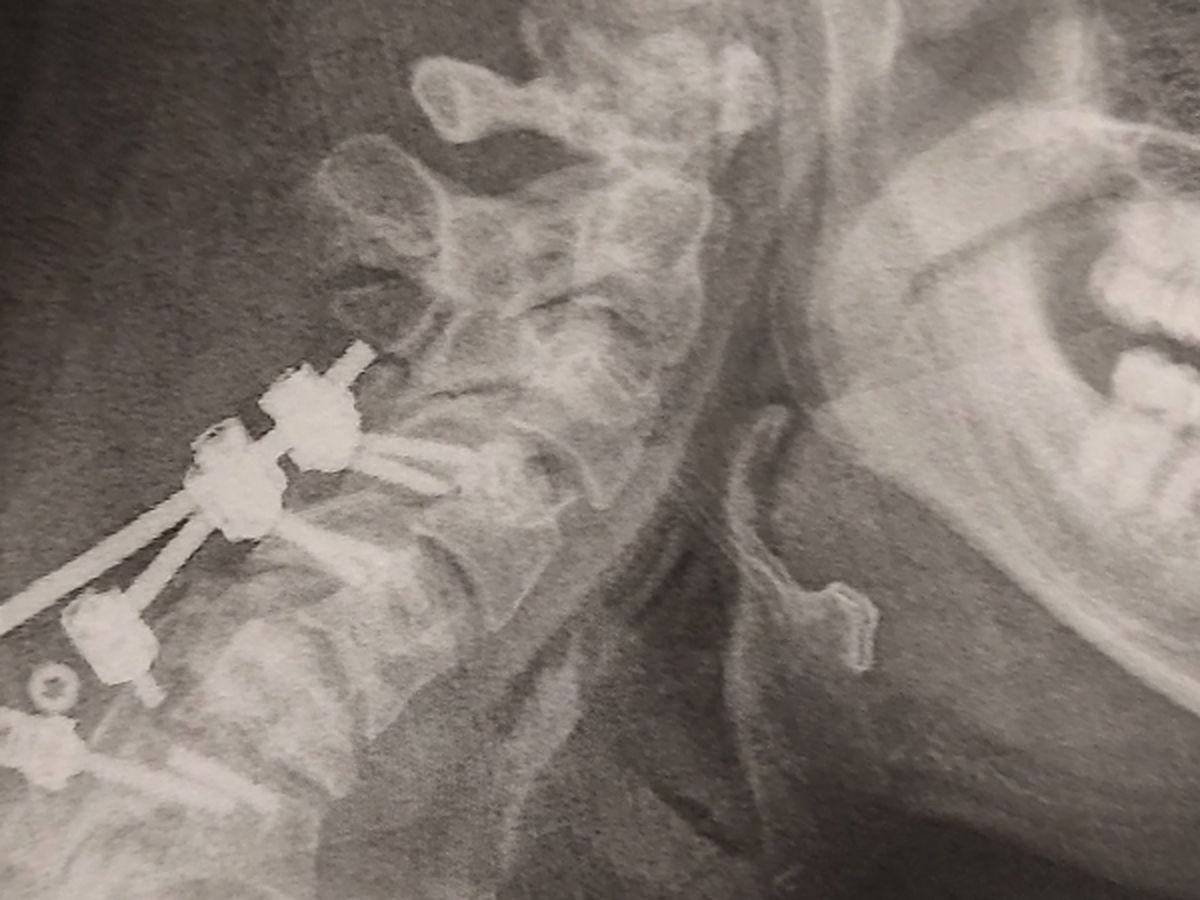

Seth has had surgery for a broken neck back in June 2025. His neck brace broke 3 times not even a month after his surgery, his recent X-ray on December 29th showed that the rod broke off the screw and has a curve starting in his neck, so he has to have surgery again sometime this month. He has not had any income so we are asking for help for his car insurance bill and keeping his phone on and just everyday living expenses food, hygiene products and some minor car repairs.